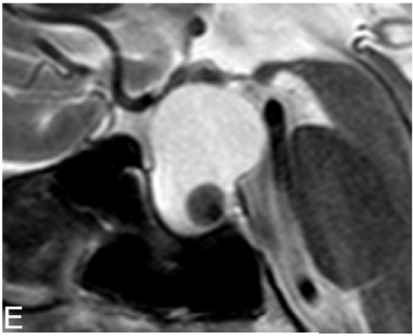

Uma mulher, 50 anos, assintomática, vem à consulta devido a um achado na ressonância magnética de hipófise. Foi observada uma imagem intrasselar, hiperintensa em T1 e T2, com nódulo intracístico, conforme a imagem a seguir:

O diagnóstico mais provável e a conduta mais adequada para este caso são, respectivamente: